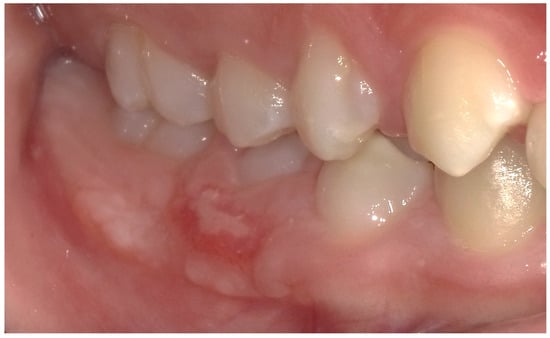

2.2. Clinical Findings

2.3. Diagnostic Assessment